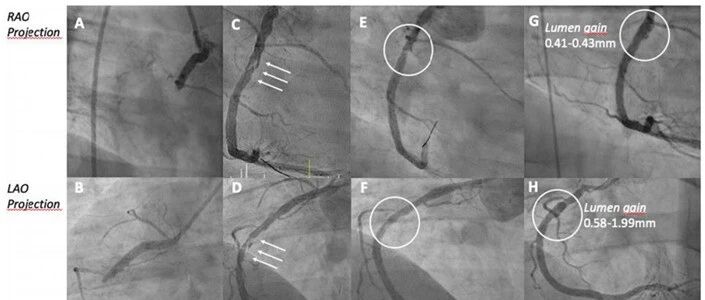

病例 | 25岁STEMI患者急诊开通RCA未植支架,药物球囊效果显著:无植入策略正在影响年轻ACS... 心在线 · 公众号 · · 3 月前 · |